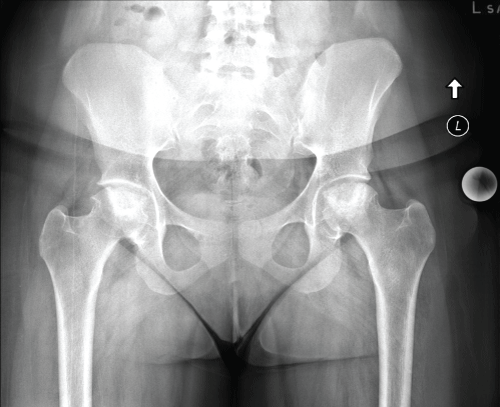

ID is an 18-year-old female, with Systemic Lupus Erythematosus (SLE) treated with long term steroids, collect and plaquenil and a history of right fibular osteosarcoma, who presented February 2015 with a one-year history of progressive activity-related bilateral hip pain. The patient described deep aching pain in the groin with radiation into the buttock and down the medial thigh on both hips. At presentation, she could no longer participate in recreational activity. She denied ever smoking and she does not use alcohol. Right hip range of motion was zero to ninety degrees of flexion, left hip range of motion was 0-100 degrees of flexion with impingement pain bilaterally. Initial Radiographs are seen in Figure 6.

Figure 6: Preoperative AP pelvis. View Figure 6

Given her history an MRI of the pelvis was done at that time showing bilateral femoral head osteonecrosis. Both femora had extensive involvement with collapse Figure 7 and Figure 8.

Six months following initial presentation she had stopped attending college due to hip pain and was unable to ambulate without assistive device (crutches). Repeat radiographs showed advancement to collapse on bilateral femoral heads (Figure 9). She was scheduled for staged bilateral total hip arthroplasty and she has done well postoperatively. Figure 10 is an intraoperative clinical photograph showing advanced femoral head collapse and postoperative radiograph showing bilateral THA after staged procedures (Figure 11).

Figure 9: Repeat preoperative AP pelvis. View Figure 9